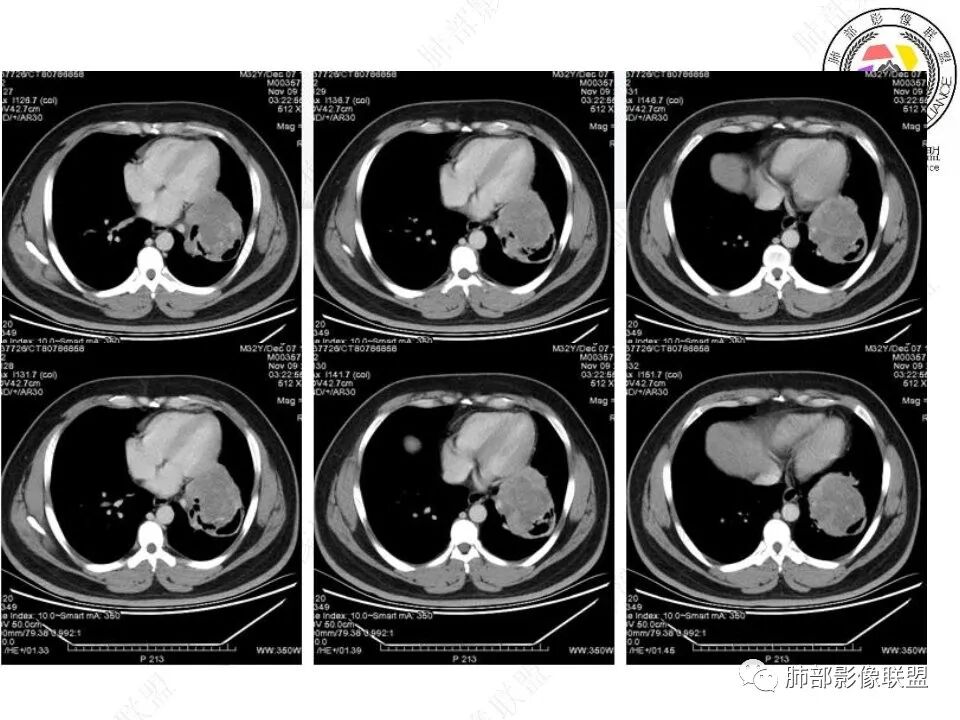

青年人,左肺下叶占位,边界清晰,支气管受包埋,病灶可见空气半月征,增强病灶内见血管影,纵膈未见增大淋巴结,考虑交界性肿瘤性病变,PSP,SFT,其次肉瘤类,鉴别淋巴瘤,小细胞癌。

青年男性,体检发现,左肺下叶肿块,边界清晰,支气管受压,病灶可见空气半月征,增强不均匀强化,内见血管穿行影,定位胸膜起源,PSP?SFT?肺内肉瘤类待排。

青年男性,体检发现左肺不规则类圆形占位性病变,叶间裂区域,定位胸膜来源。左肺下叶支气管受压狭窄,但管壁光整,未见腔内阻塞或管壁受侵。包块边界清晰,浅分叶,内部密度不均匀,病灶后份见空气新月征。渐进性强化,增强动脉期见分支状血管,蛇纹血管征。肺门纵膈未见增大淋巴结,符合孤立性纤维瘤(SFT)。

3)肺部SFT好发于肺表面如叶间裂等区域,定位相当重要。肿块边界清楚光整,支气管不受侵(或可受压推移)。CT平扫肿瘤多呈等或稍低密度。发生于脑膜的SFT平扫肿瘤多为略高密度病,类似脑膜瘤;肿瘤较小者密度均匀,较大者内部密度常不均匀、见多发灶性或不规则形中心低密度区(细胞稀疏区含有丰富胶原纤维易发生黏液样变性或囊性变),钙化少见。

5)肿瘤的强化程度及方式:增强扫描肿瘤早期实性成分呈不均匀斑片或斑驳样强化,亦可呈“ 地图样” 明显强化,强化程度不一,可呈轻度-显著强化;静脉期持续强化,多期增强及动态增强扫描均呈“快进慢出”型强化,且强化范围逐渐增大并趋均匀。肿瘤内部及周围常见多发粗细不等强化或流空肿瘤血管影。瘤体内“蛇纹血管”在其他诸如硬化性肺细胞瘤、错构瘤等等是非常罕见的。